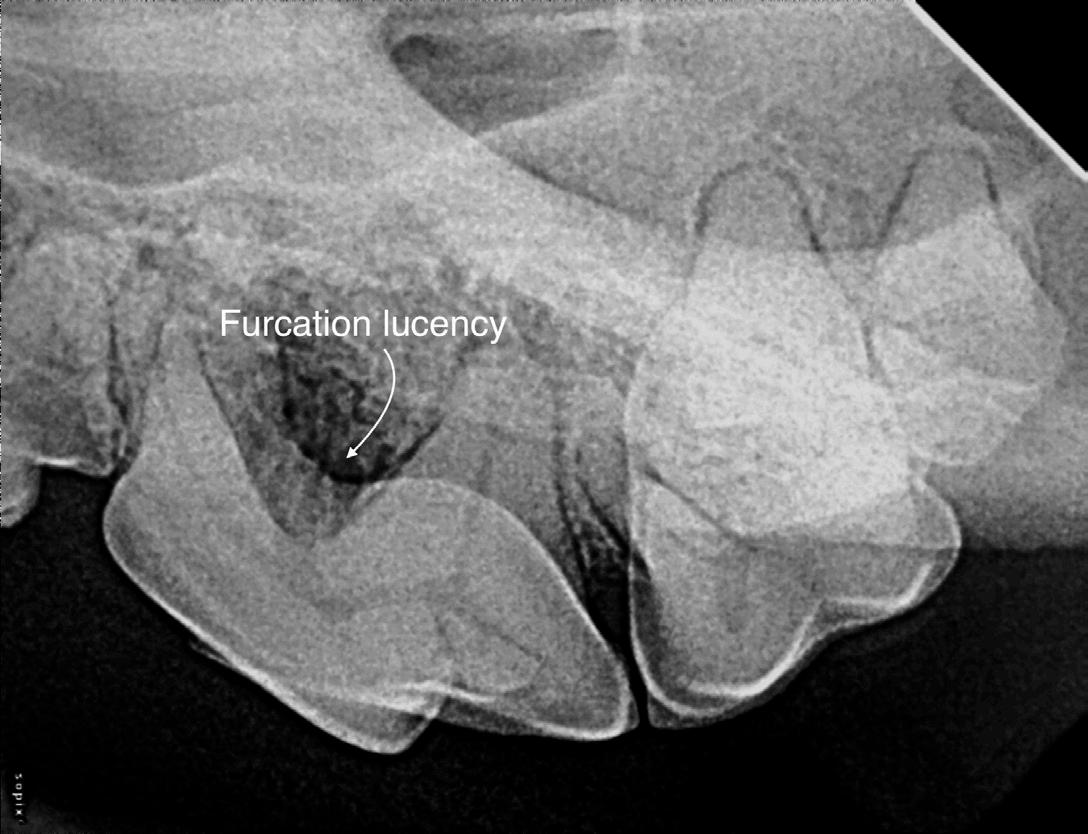

Furcation involvement and exposure results from bone loss at the root junction of multi-rooted teeth. It is sometimes difficult to determine radiographically whether the interradicular space is involved unless there is a radiolucent area in the region of the furcation. Lack of radiographically detectable furcation involvement is not confirmation of the absence of periodontal destruction. Advanced furcation through-and-through exposures, where both cortical plates are resorbed, are easily recognized on radiographs.

Figure 3: Early and moderate periodontal diseases. Image courtesy of Dr. Jan Bellows. Figure 4: Furcation exposure consistent with advanced periodontal disease. Image courtesy of Dr. Jan Bellows.